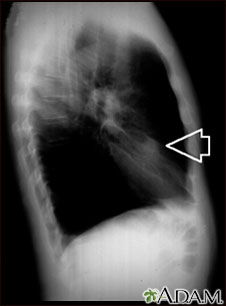

This is a chest x-ray (CXR) of a nodule in the right lung.